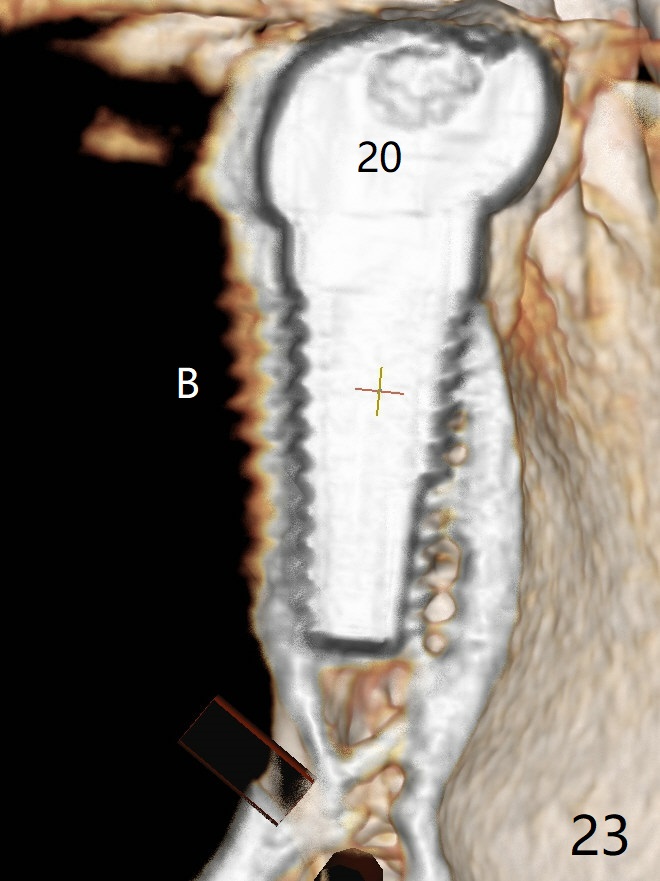

Two of 2.5 mm 1-Piece Implants M

The edentulous ridge at #30 is narrow (Fig.1). After ridge reduction, osteotomy is initiated with 1.2 mm drill for 10 mm; the mesial osteotomy is to be changed (Fig.2 red line). Using a 1.2 mm drill placed in the distal osteotomy (Fig.3 D), the mesial osteotomy changes in trajectory with subsequent placement of a 2.5x10(4) mm 1-piece implant. Since the mesial implant is high in occlusion, the cuff of the distal implant is changed to be 2 mm (Fig.4 (shorter black line)). Panoramic X-ray is taken to show no violation of the Inferior Alveolar Canal (Fig.5 red dashed line). These two 1-piece implants are slightly lingually placed (Fig.6). The crestal bone around the implants resorbs without thread exposure 5 months postop (Fig.7). Impression is taken for a splinted crown (Fig.8-12). There is no metal show around the 2.5 mm 1-piece implants 6 months postop (advantage) vs. that at #28 and 29 (Fig.13). Bitewing is taken post cementation to determine whether residual cement is present (Fig.14). There is periodic swelling and pain in the lower right quadrant 2 years post cementation (Fig.15). In fact periimplantitis appears to have developed at #28 (Fig.16) with loss of the buccal bone (Fig.17,18). The buccal bone loss is less at #29 (Fig.19) and #20 (Fig.23) and no at #30 mesial and distal implants (Fig.20,21). A much smaller implant will be placed lingually at #28 immediate (Fig.24,25).